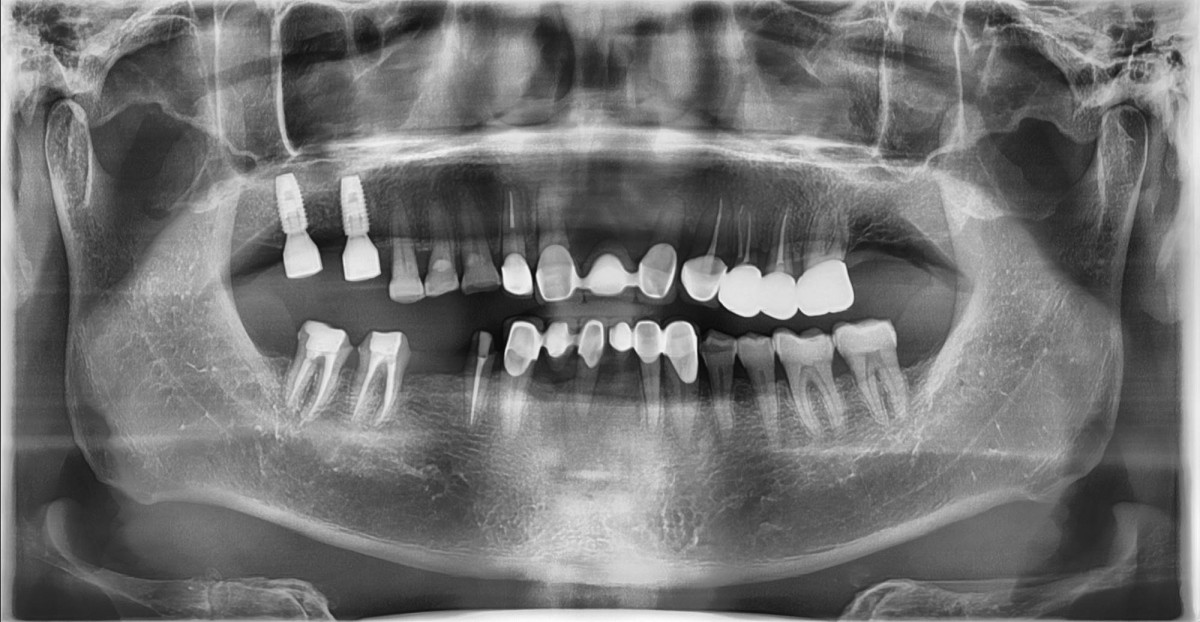

Socket Lift and Implant Placement in the right maxilla.

<GCacg> A 56-year-old male patient complained of pain in the right upper and lower jaws. And he wanted the upper first molar to be pulled out first.